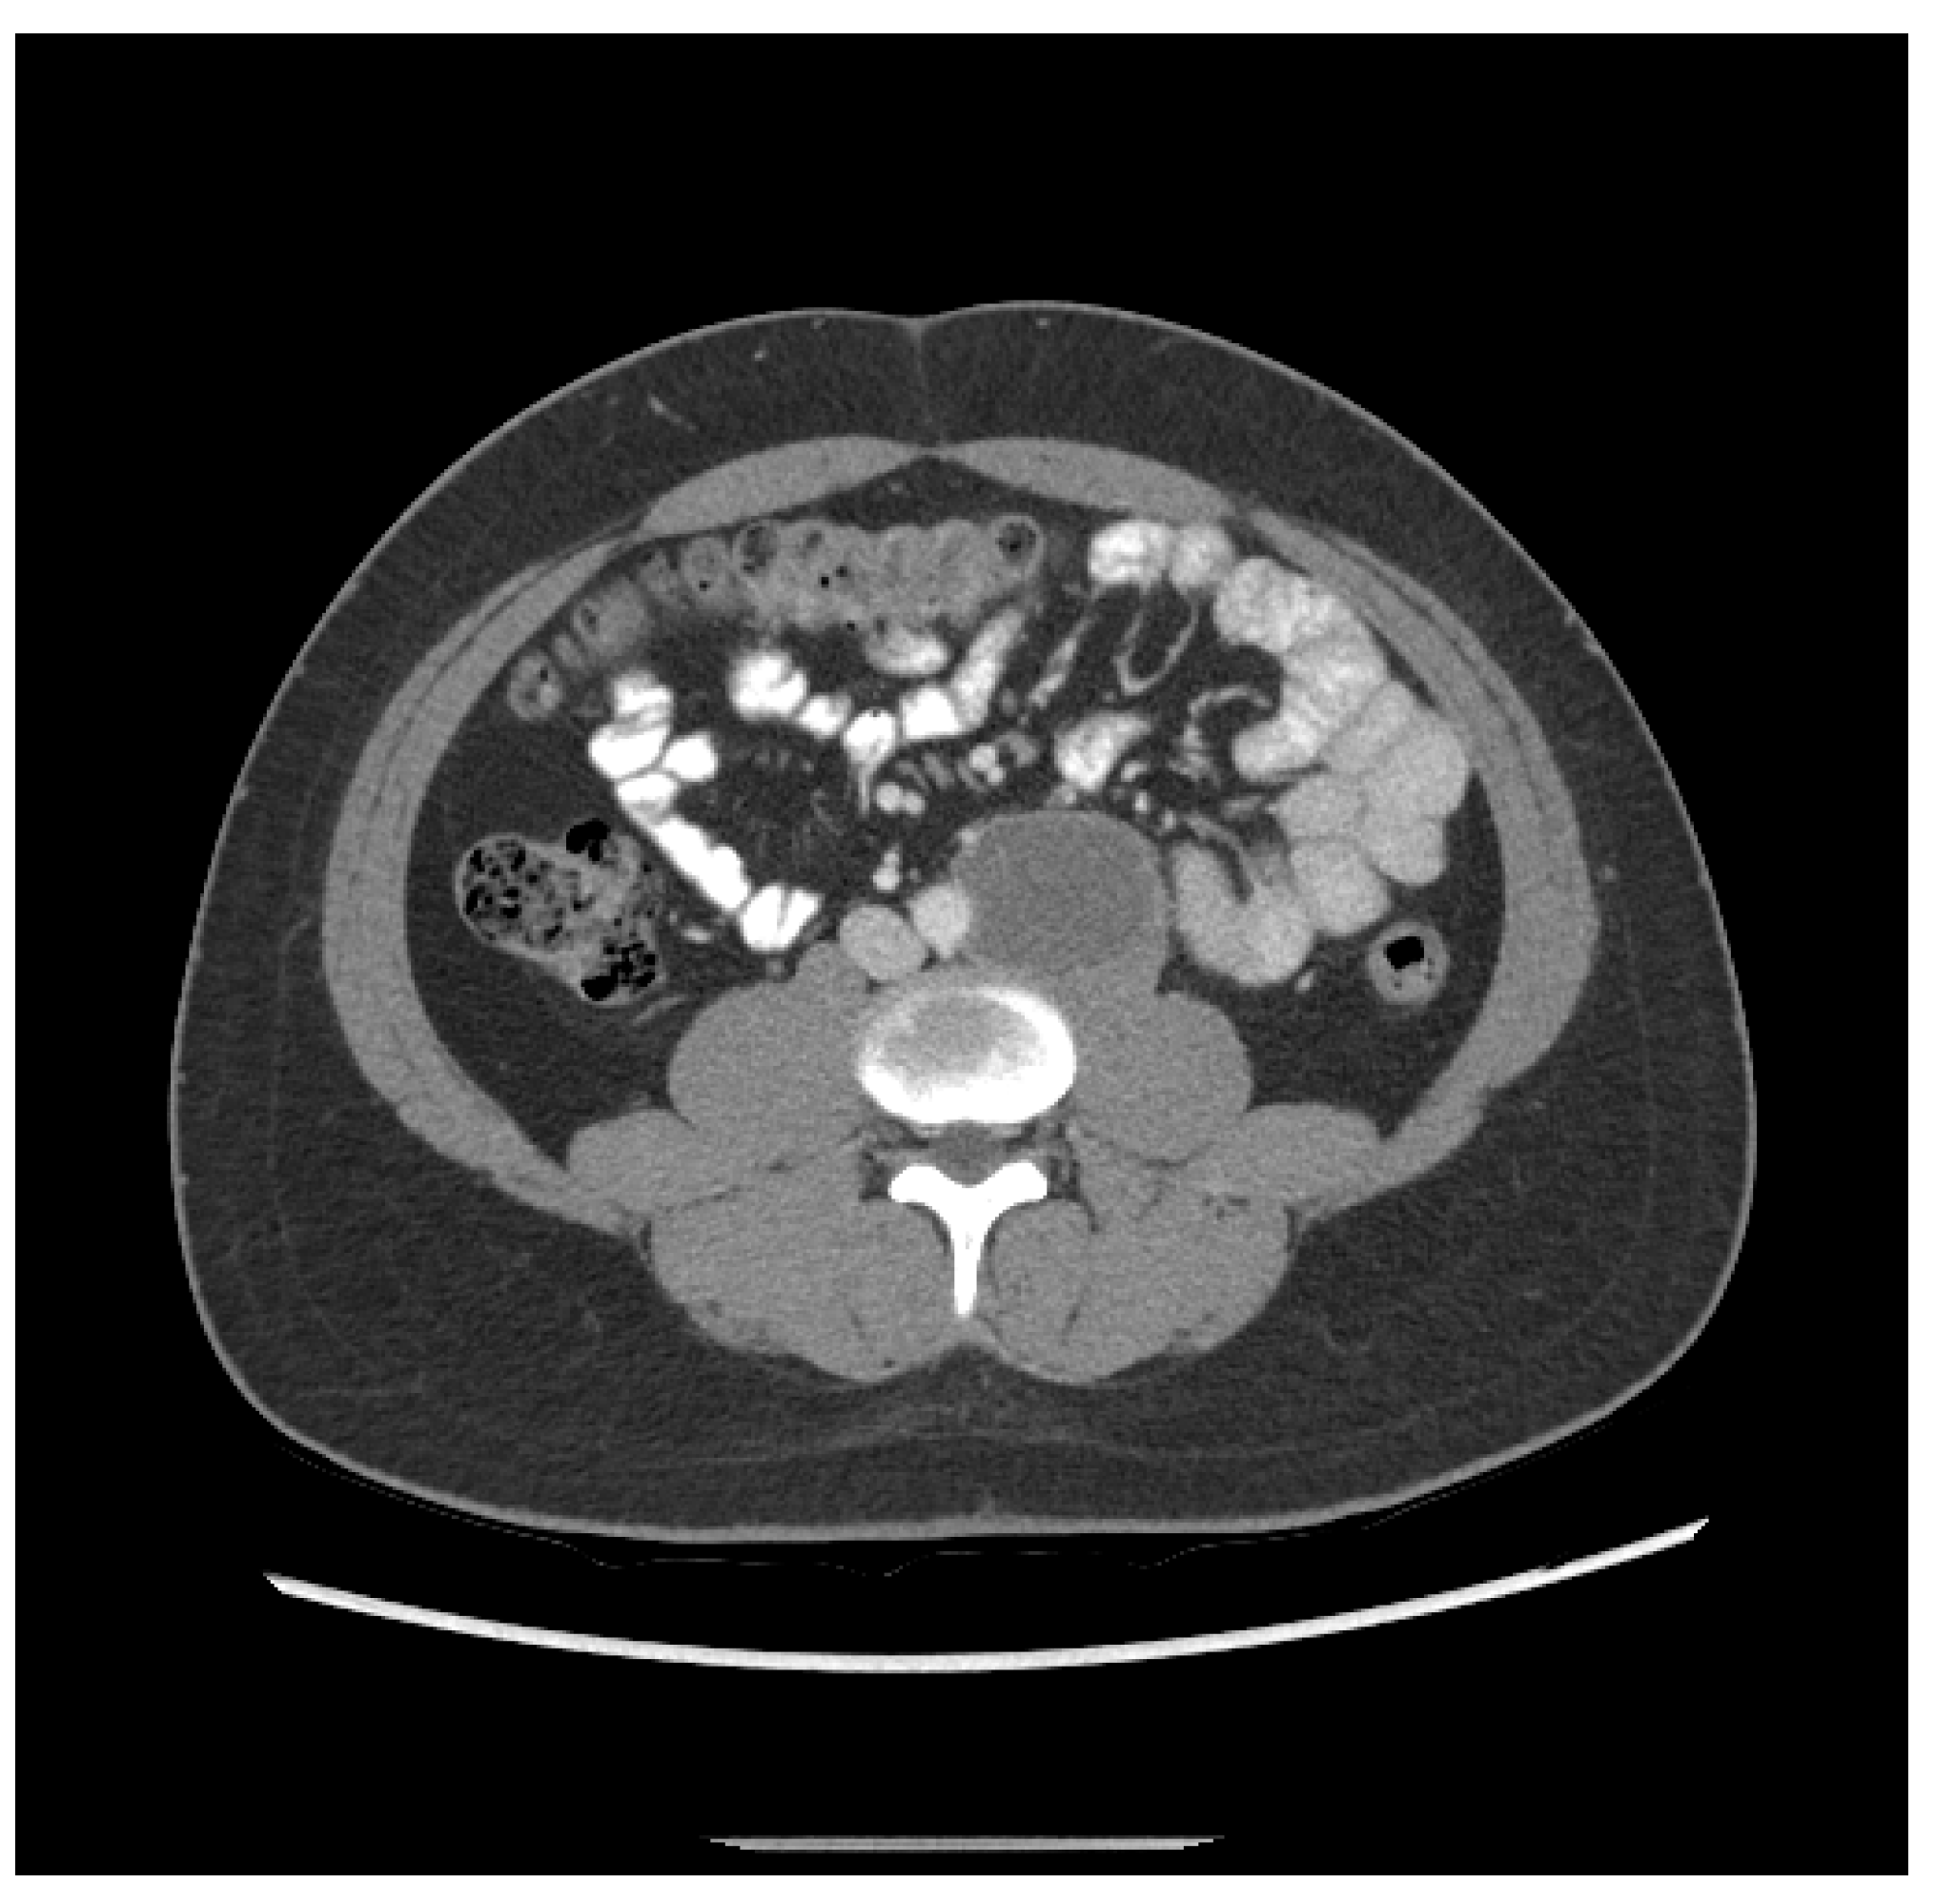

3. The patient was a 20-year-old Hispanic male who complained of back pain for one week and presented to the local emergency department, which found a retroperitoneal mass measuring 6.3 cm and a left testicular mass. He then underwent a left radical orchiectomy. Pathology showed 80% epithelial trophoblastic tumor and 20% teratoma. He received three cycles of BEP. Staging CT after two cycles of BEP revealed shrinkage of the retroperitoneal mass to 5.2 cm (Figure 2). His initial tumor markers were unavailable; however, initial post-treatment HCG was 81.7 mIU/mL.

Figure 2.

Patient ETT 3 with residual retroperitoneal lymphadenopathy after frontline chemotherapy.